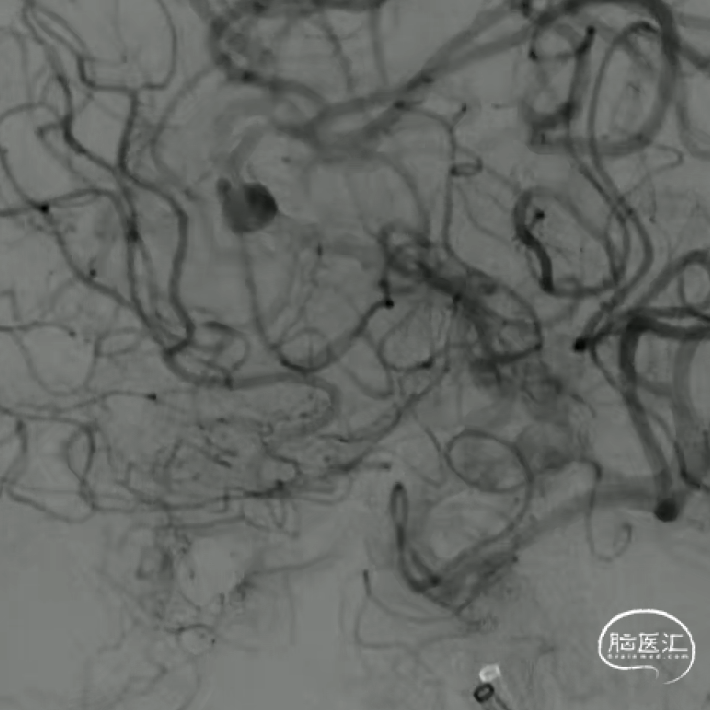

如意中段释放

心玮“如意”血流导向密网支架相较于其他钴铬合金材质,密网支架略软,释放远端动脉瘤不会影响血管的走形。

中段释放后,造影,动脉瘤滞留明显,支架贴壁打开良好,支架位置合适。

如意完全释放

支架整体释放后,贴壁良好,打开良好,无需再次按摩支架贴壁,故上高心玮DMC21微导管,回收带镍钛球囊的输送导丝。

术后即刻造影,动脉瘤滞留明显,载瘤动脉管腔通畅无狭窄,支架贴壁理想。

“如意”血流导向密网支架很好打开,镍钛小球助力支架更好的二次打开,支架释放中就能达到自膨打开,无需按摩,是一款各方面性能都不错的支架。

本例病例奇大脑前A3段动脉瘤,从大脑前动脉瘤起始段有广泛伴有动脉粥样硬化的斑块,血管路径过于迂曲,且颅内支撑导管的位置过低,仅位于C4段,无法提供很好的支撑性和力的传导功能,这样的情况会导致支架推送性能会有下降,释放中会降低可控性,对于这样的病例,颅内支撑导管上到更高,上至颈内动脉瘤末端或A1段会起到更好的帮助。